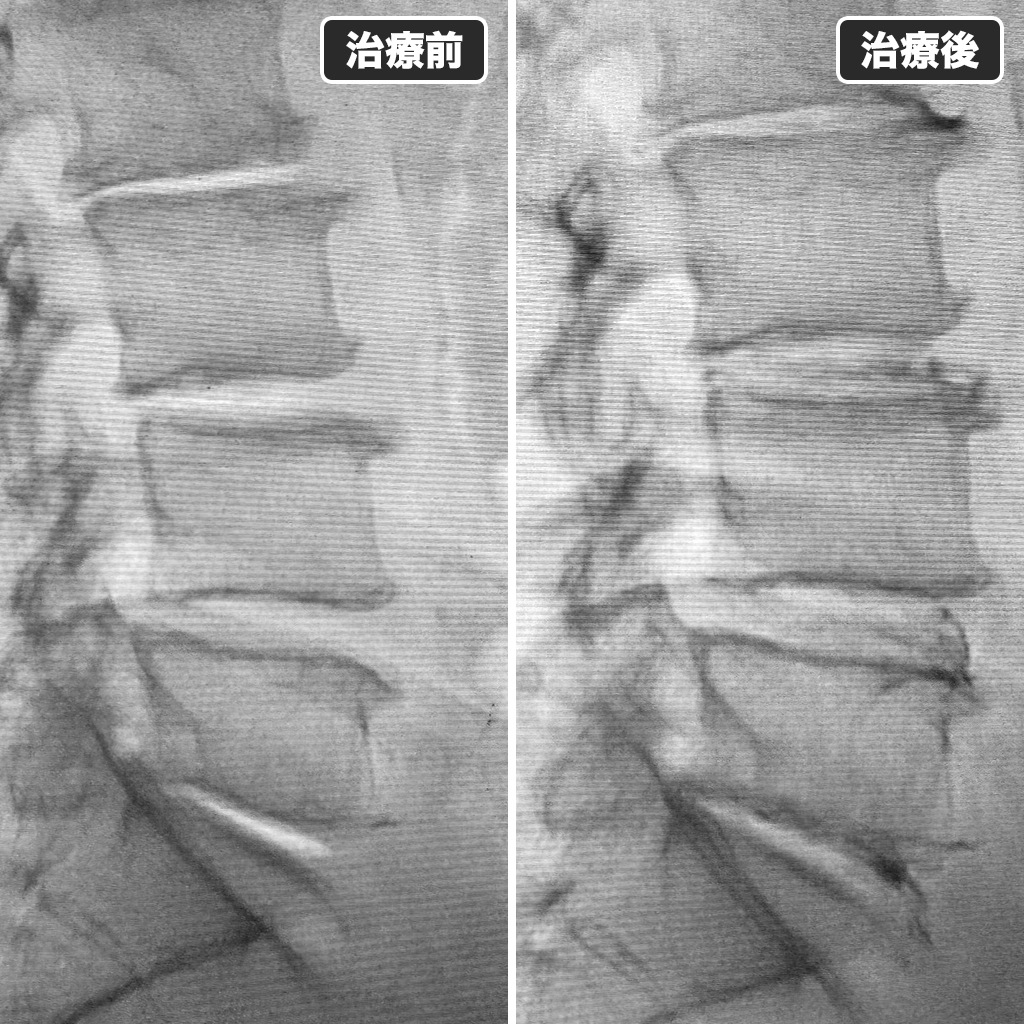

治療前後のレントゲン写真

治療前後のレントゲン写真になります。左側が治療前で右側が治療後になります。